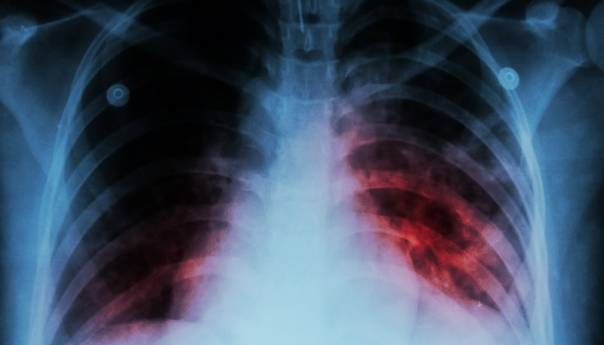

Nakon COVID-19, tuberkuloza je najsmrtonosnija zarazna bolest na svijetu. Uzrokuju ga bakterije koje obično pogađaju pluća. Klice se uglavnom prenose s osobe na osobu u zraku, na primjer kada zaražena osoba kašlje ili kiše.

Iako je moguće liječiti zahvaljujući naučnim istraživanjima, tuberkuloza i dalje svake godine uzima veliki broj života širom svijeta.

Prema Svjetskoj zdravstvenoj organizaciji, oko 10,6 miliona ljudi, uključujući 1,2 miliona djece, oboljelo je u 2021. godini u svijetu, a umrlo je 1,6 miliona.